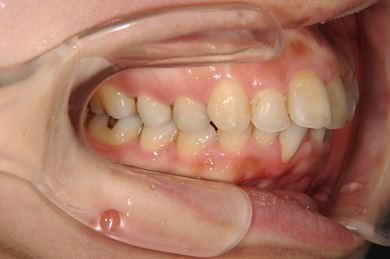

セラミックの症例写真 SHINBI

インプラント矯正治療+セラミック治療

| 性別/年齢 | 女性 / 35歳 | ||||||||||||||||||||||||||||||||

| 主訴 | 歯並び(乱ぐい歯、出っ歯)と歯の色が気になる。 | ||||||||||||||||||||||||||||||||

| 治療方針 | 左上の第一大臼歯がすでに抜歯され欠損の状態で来院されました。デンタルインプラント、あるいはブリッジで補綴するよりも、上あごが突出していること、乱杭歯があることより、矯正治療を第一選択としました。上下第一小臼歯を4本抜歯してその隙間を利用し、治療していきました。抜歯スペースをすべて効率的に利用したいため、上顎左右、下顎左側1本の計3本のインプラントアンカーを使用します。左上は第二大臼歯、智歯を利用しています。今後保定装置の針金は一生装着予定です。上顎の中切歯は左右とも人工的にかぶせものをしています。初診の歯牙変色がなくなり、審美的にもとてもよくなりました。 | ||||||||||||||||||||||||||||||||

| 治療内容 | インプラント矯正(唇側矯正ホワイト、審美ワイヤー、左右上顎第一小臼歯抜歯、上顎インプラントアンカー) | ||||||||||||||||||||||||||||||||

| 治療期間 | 1年9ヶ月 |